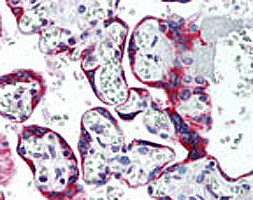

Supportive validation

- Submitted by

- Abnova Corporation (provider)

- Main image

- Experimental details

- IHC analysis of human placenta. Using SSTR5 polyclonal antibody (Cat # PAB0299) at 10 ug/mL .

- Validation comment

- Immunohistochemistry